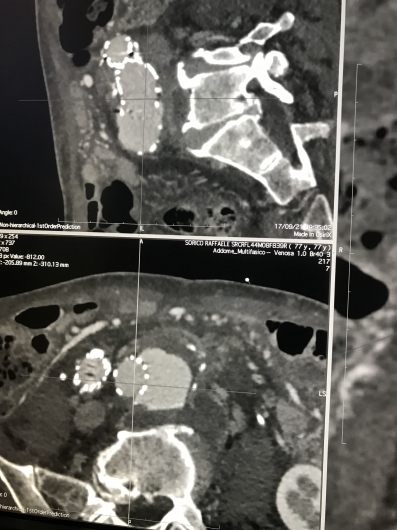

Dirigente Medico di ruolo presso U.O.C. Chirurgia Vascolare ed Endovascolare Ospedale San Giovanni di Dio e Ruggi d’Aragona di Salerno. Pratica attività ambulatoriale, laboratorio di diagnostica ultrasonografica, diagnostica angiografica e attività di sala operatoria (chirurgia open ed endovascolare). L’attività chirurgica tradizionale ed endovascolare comprende il trattamento delle lesioni stenotiche/ostruttive dei tronchi sovraortici (carotidi), lesioni stenotiche/ostruttive delle arterie periferiche e viscerali, degli aneurismi dell’aorta e aneurismi periferici e viscerali (sia in elezione che in urgenza), inoltre l’attività chirurgica comprende il trattamento della patologia venosa (vene varicose/varici) secondo le tecniche chirurgiche classiche (es. stripping) e moderne (laser, radiofrequenza, scleroterapia maggiore), scleroterapia minore di teleangectasie e vene reticolari (estetica vascolare).